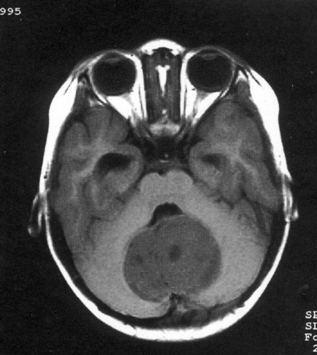

问题 病历摘要:??患儿男性,11岁。半年前开始出现行走不稳,常无故跌倒。半月前出现发作性剧烈头痛,伴恶心呕吐。体检:T36℃,P100次/分,R22次/分,BP100/60mmHg,神清,言语较缓慢,双眼外展约不及边,双眼侧视时有小幅度水平眼震。四肢肌力正常,右上肢肌张力较低,坐位姿势不稳,常不自主摇晃,双上肢指鼻不准,行走蹒跚步态,足距扩大,身前倾。 初步诊断考虑哪些疾病?提示:患儿行头颅?MR检查(见图)

选项 A.室管膜瘤 B.转移瘤 C.淋巴瘤 D.髓母细胞瘤 E.血管网状细胞瘤 F.星形细胞瘤 G.脉络丛乳头状瘤 H.多形胶质母细胞瘤

答案 ADFG